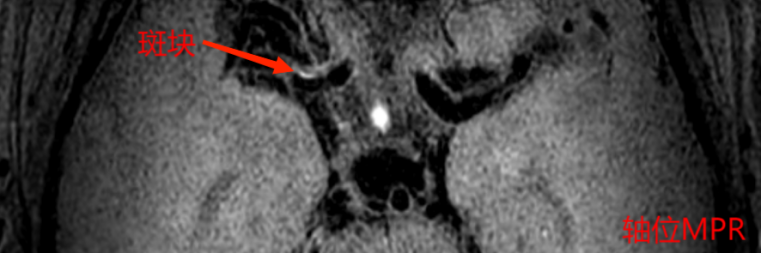

以上4图平扫的T1W-VISTAT2WT1W-3D-SNAP都发现大脑中动脉M1段的大小为1.2*1.5*2.8mm等低信号斑块。

6c7180e7ed935be81a1d0dac685b2bb3.pngf8d20e7e820aa9111b30f3e48b62d51c.png

上图是打药后扫描的T1W-VISTA+C图像,斑块表现为轻度强化,综合考虑为不稳定斑块。这种情况需要慎重处理,斑块破裂和脱落风险比较大,建议经药物治疗后随访复查。